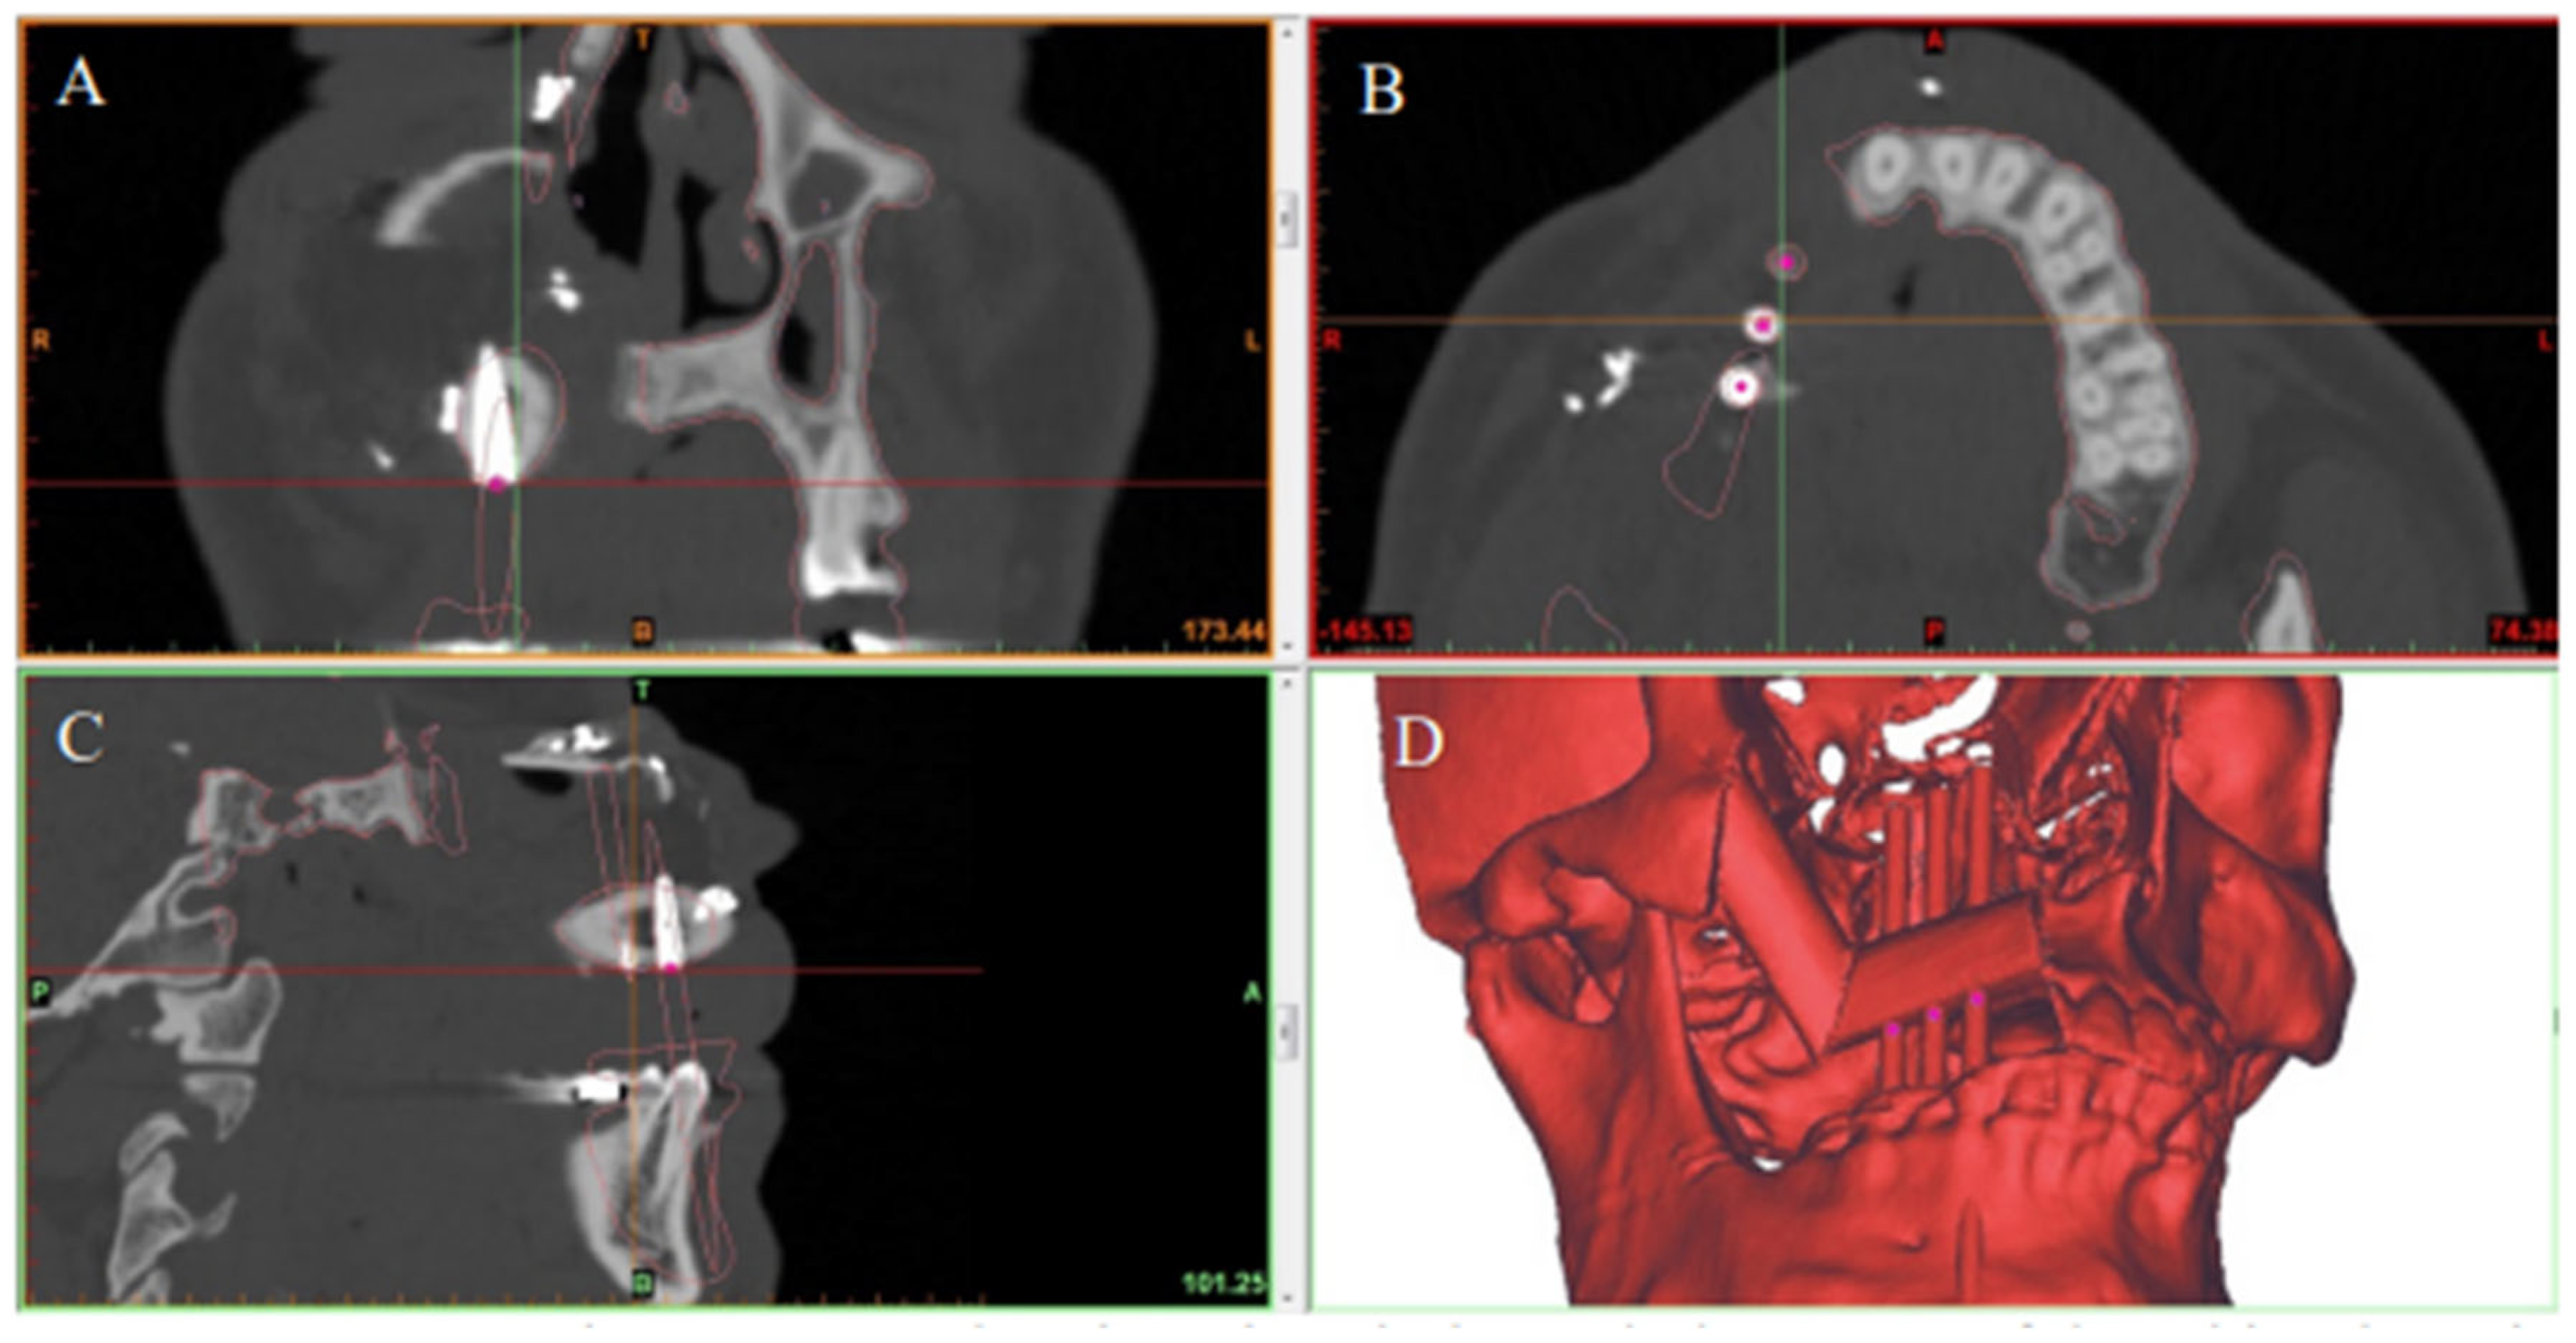

2.3. Virtual Surgical Planning

2.4. Surgical Procedure

2.4.1. Stage I: Flap Prefabrication

2.4.2. Stage II: Jaw Reconstruction